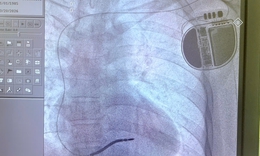

Cứu sống bệnh nhân vỡ động mạch chủ bụng bằng Stent graft

Y tế - 10/10/2025 14:54SKĐS - Vừa qua, các bác sĩ Bệnh viện Hữu Nghị đã cứu sống một bệnh nhân 76 tuổi bị vỡ túi phình kích thước gần 8cm (động mạch chủ) bằng kỹ thuật can thiệp nội mạch hiện đại, đây là một tình trạng cấp cứu y khoa có tỷ lệ tử vong cao.